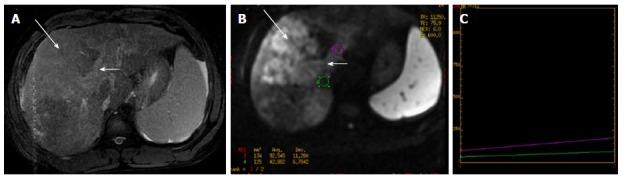

"Personalized oncology" is a multi-disciplinary science, which requires inputs from various streams for optimal patient management. Humongous progress in the treatment modalities available and the increasing need to provide functional information in addition to the morphological data; has led to leaping progress in the field of imaging. Magnetic resonance imaging has undergone tremendous progress with various newer MR techniques providing vital functional information and is becoming the cornerstone of "radiomics/radiogenomics". Diffusion-weighted imaging is one such technique which capitalizes on the tendency of water protons to diffuse randomly in a given system. This technique has revolutionized oncological imaging, by giving vital qualitative and quantitative information regarding tumor biology which helps in detection, characterization and post treatment surveillance of the lesions and challenging the notion that "one size fits all". It has been applied at various sites with different clinical experience. We hereby present a brief review of this novel functional imaging tool, with its application in "personalized oncology".

“个性化肿瘤学”是一门多学科科学,为实现最佳的患者管理,需要各个领域的投入。现有治疗方式取得了巨大进展,除形态学数据外,提供功能信息的需求也日益增加,这推动了成像领域的飞跃发展。磁共振成像随着各种更新的磁共振技术取得了巨大进步,这些技术提供了至关重要的功能信息,并正成为“放射组学/放射基因组学”的基石。扩散加权成像就是这样一种技术,它利用了水质子在给定系统中随机扩散的趋势。这项技术通过提供有关肿瘤生物学的重要定性和定量信息,彻底改变了肿瘤成像,有助于病变的检测、特征描述和治疗后监测,挑战了“一刀切”的观念。它已在不同部位应用,并积累了不同的临床经验。在此,我们简要综述这一新型功能成像工具及其在“个性化肿瘤学”中的应用。